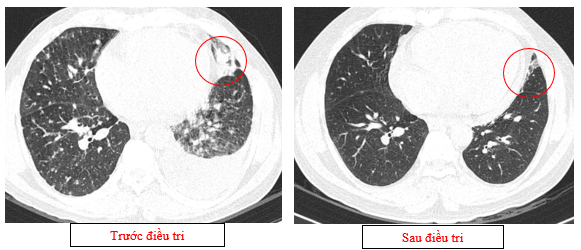

Hình 02: Khối rốn phổi trái ôm quanh nhánh phế quản thùy dưới trái kích thước 28x26mm, dày tổn chức kẽ vách liên tiểu thùy và nhiều nốt đặc lan tỏa khắp nhu mô, đường kính <7mm.

Hình 08: Khối u đáp ứng gần hoàn toàn,chỉ còn tổn thương dạng kính mờ, các tổn thương dày tổ chức kẽ vách liên tiểu thùy, nốt đặc rải rác 2 trường phổi cũng gần như biến mất